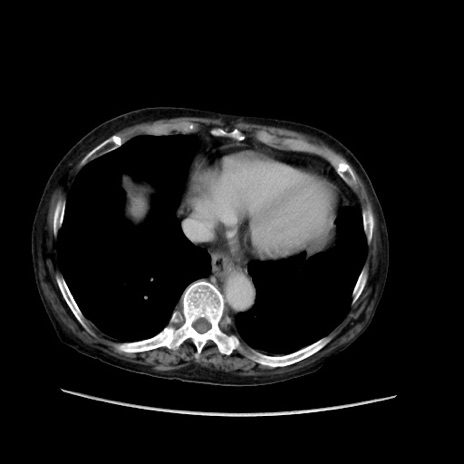

症例31(横断像)

【症例】80歳代 女性

【主訴】腹部膨満感

【現病歴】他院にて肝硬変にてフォロー中。1週間前から便秘、腹部膨満感、臍部腫瘤あり受診となる。

【既往歴】肝硬変

【身体所見】腹部膨隆あり、皮膚変化なし、疼痛なし。

【データ】WBC 4600、CRP 0.25